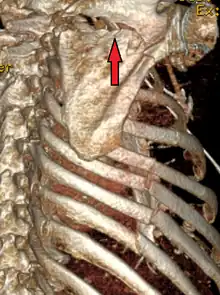

A right sided scapula fracture with rib fractures underneath seen on a 3D reconstruction of a CT scan

Most fractures of the scapula can be seen on a chest X-ray; however, they may be missed during examination of the film.[1] Serious associated injuries may distract from the scapular injury,[4] and diagnosis is often delayed.[3] Computed tomography may also be used.[1] Scapular fractures can be detected in the standard chest and shoulder radiographs that are given to patients who have had significant physical trauma, but much of the scapula is hidden by the ribs on standard chest X-rays.[4] Therefore, if scapular injury is suspected, more specific images of the scapular area can be taken.[4]